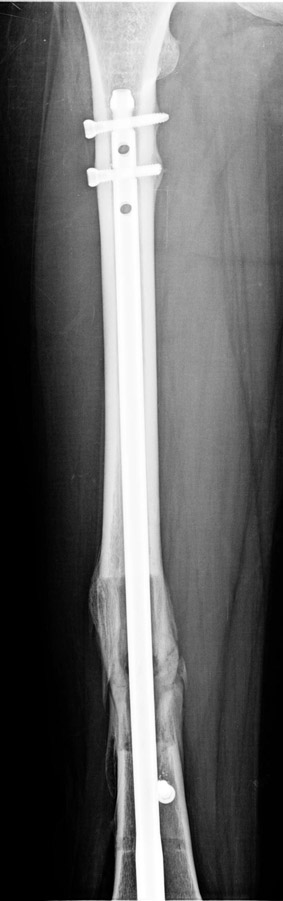

In selected cases, we prefer to use a combination of a unilateral dynamic axial fixator and an interlocked intramedullary nail, in order to protect the length and alignment after the completion of the lengthening procedure. As a prerequisite for this technique, the narowest diameter of the medullary cavity shall be wider than 7 mm and the length of the nail segment distal to the osteotomy site shall be at least 8 cm. after the completion of the lengthening procedure.The intramedullary nail neutralizes shear and bending forces on femur during lengthening, shortens external fixation time, and protects newly formed bone against fractures. In our series, subtrochanteric osteotomy was performed in one case. No varus angulation occured despite the intramedullary nail.

Ilizarov stressed the significance of endosteal blood circulation for distraction osteogenesis. Although we placed the intramedullary nail after reaming the femur in all cases, the time for callus formation was not longer than expected. Thus we found that there is no slowing in the rate of new bone formation due to disruption of medullary blood flow. The rationale of this finding is revascularization that occurs following reaming of the medullary cavity, the fixation stability with the intramedullary nail and early functional weight bearing. The potential disadvantages of a combined use of external and internal fixation metods are increased blood loss, intramedullary infection, risk of fat embolism and excessive metal load.The most fearsome complication is a deep intramedullary infection (panosteomyelitis) triggered by pin tract infection.No such complication was encountered in our series. In order to avoid this complication, after the completion of lengthening the nail shaill be interlocked from the medial side, and contact of internal and external fixator pins shall be avoided.

The combination of intramedullary anil and dynamic axial external fixator is harder as a technique than Standard Ilizarov applications. However, it is stil appealing due to the following advantages: shortening of the duration of external fixation, protection against refracture, early rehabilitation, gaining maximum range of motion and daily quality of life. These advantages are more important than disadvantages such as increased cost, increased blood loss and potetntial deep infection. All in all, we believe that the technique of femoral lengthening over an intramedullary nail is a safe and reliable method and provides advantages over standard Ilizarov aplications.